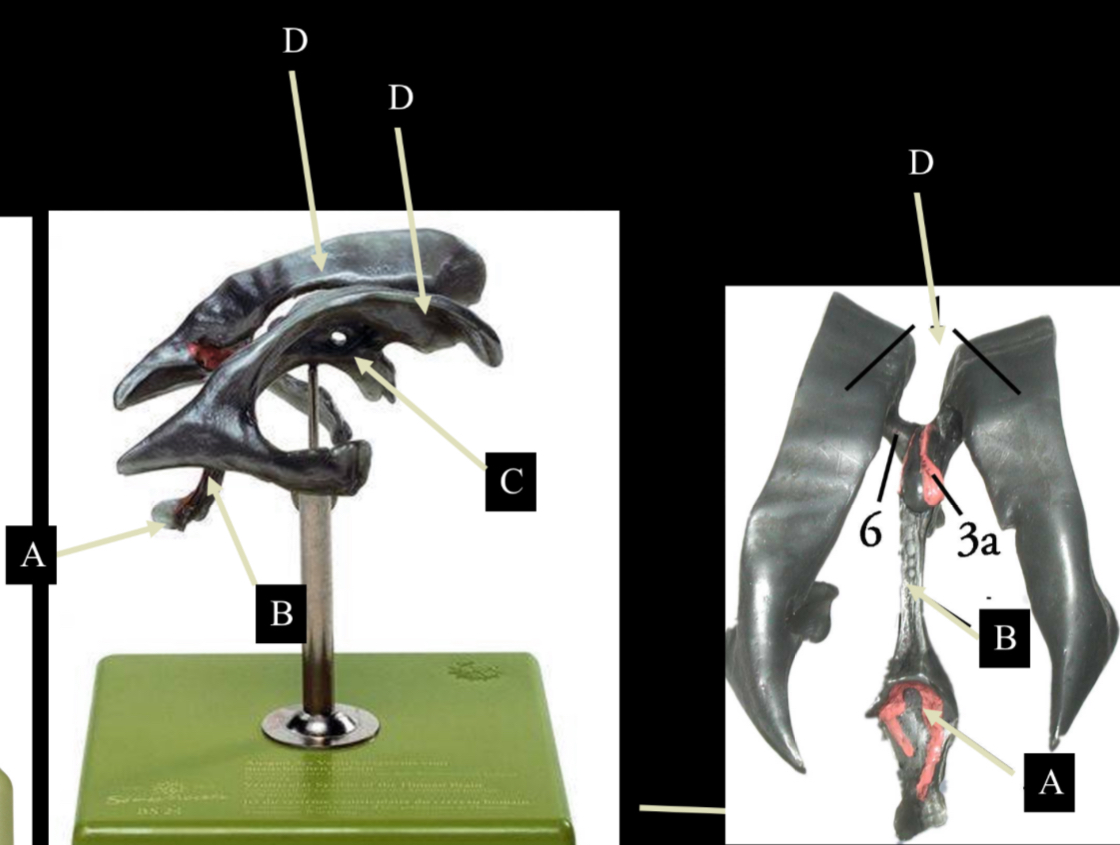

What is D?

lateral ventricle

Imagine thin membrane separating the 2 lateral ventricles

septum pellucidum

What is C?

3rd ventricle

What is B?

cerebral aqueduct

What is A?

4th ventricle

What is below A at the very end?

central canal (spinal cord)